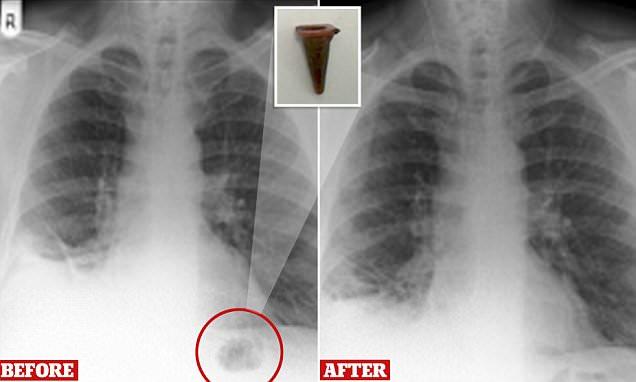

لندن .....  ڈاکٹروں وغیرہ سے بھی اندازے کی طرح طرح کی غلطیاں سرزد ہوجاتی ہیں جو اکثر خبروں کاموضوع بنتی ہیں اور جسے کچھ لوگ دلچسپی کیلئے پڑھتے ہیں تو کچھ اس سے سبق حاصل کرنے یا حفظ ماتقدم کے طور پر تیار رہنے کیلئے کرتے ہیں۔ ایسا ہی کچھ یہاںایک 47سالہ شخص کے ساتھ اس وقت پیش آیا جب اسکے منہ سے جما ہوا  پیلا بلغم خارج ہورہا تھا اور جب یہ صورت تکلیف دہ حد تک ہوگئی تو اس نے ڈاکٹروں سے رجوع کیا۔ اسپتال میں اس کے پھیپھڑوں کی اسکیننگ کی گئی اور ڈاکٹروں نے اندازہ لگایا کہ جو علامتیں نظرآرہی ہیں  او راسکیننگ میں جو تصویر نظرآرہی ہے وہ کسی سرطان زدہ رسولی کی ہے۔ ڈاکٹروں نے فوری طور پر اس شخص کو جو تمباکو نوشی کرتا تھا کسی اچھی جگہ اسکیننگ کیلئے بھیجا  تو وہاں سے نفی میں جواب آیا۔ بڑے اسپتال کے ڈاکٹروںنے بعد میں  اس بات کا تعین کرلیا کہ نظرآنے والی چیز رسولی نہیں بلکہ کسی پرانے کھلونے کا کون نما ٹکڑا ہے۔اطلاعات کے مطابق پرسٹن میں رہنے والے اس شخص نے ذہن پر زو ردیتے ہوئے بتایا کہ اب سے 40سال قبل اس نے یہ ٹکڑا نگل لیا تھا۔ یہ تحقیقی رپورٹ برٹش میڈیکل جرنل کے تازہ شمارے میں طبی اسرار کے عنوان سے شائع ہوئی ہے۔